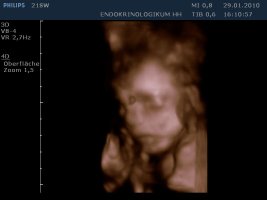

Gestern haben Sunny und ich uns erfolgreich als Versuchskanninchen für die Dopplersonographie betätigt und als Belohnung gab's 3/4D.

Das ist unser kleiner Kerl - mein Mann und ich sind hin und weg :love1

Anhänge

• 10-01-29-160926_21SW_20100129_161354_0001.jpg

10-01-29-160926_21SW_20100129_161354_0001.jpg

26,6 KB · Aufrufe: 416

• 10-01-29-160926_21SW_20100129_161354_0000.jpg

10-01-29-160926_21SW_20100129_161354_0000.jpg

26,4 KB · Aufrufe: 411